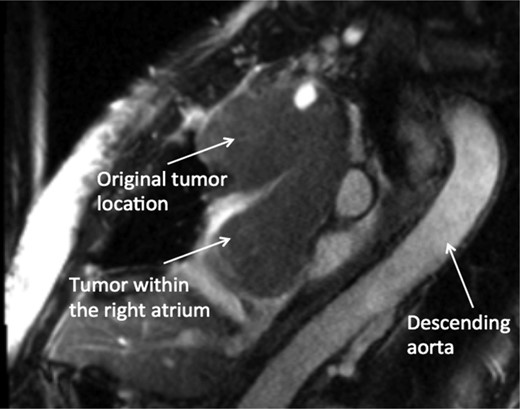

A 74-year-old female presented with facial and upper extremity swelling over the last month. The swelling was worse in the morning and improved throughout the day. The patent also reported dyspnea on exertion. A review of systems was otherwise negative. Social history was notable for 40-pack-year smoking history, but she quit smoking 12 years ago. Her vital sign were stable. Physical examination revealed mild facial swelling, non-pitting edema of the upper extremities and distention of superficial veins of the anterior chest wall and jugular veins. There were no significant laboratory abnormalities. An echocardiogram showed moderate right atrial dilation with a mobile mass in the atrial cavity prolapsing through the tricuspid valve, bowing of atrial septum from right to left consistent with increased right atrial pressure, moderate tricuspid regurgitation and normal left ventricular ejection fraction with no regional wall motion abnormalities. Cardiovascular magnetic resonance imaging revealed a 9.9 × 4.3 cm heterogeneous mass admixed with thrombus in the anterior mediastinum compressing the SVC and endovenously extending into the right atrium (Figs 1–3). Anticoagulation with heparin drip was initiated. A computed tomography (CT)-guided biopsy revealed a tan-colored mass with CD5 lymphocyte predominance, inconspicuous epithelial cells positive for P63 expression and cytokeratin AE1/AE3 that was morphologically consistent with thymoma type B1.

CMR coronal view: anterior mediastinal mass invading superior vena cava and extending into the right atrium.